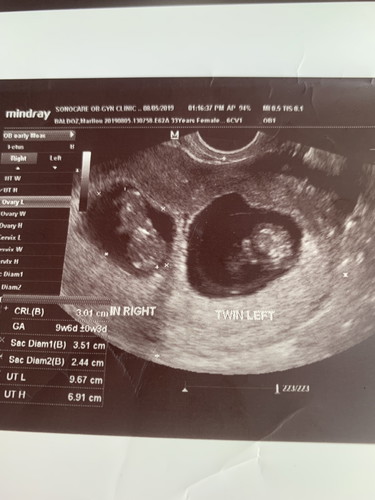

Hello po nais ko lang po sna mag tanung 2 10weeks pregnant ko ako ngayun...lage po sumasakit ang ulo ko at lage di aq nakakatulog sa gabi...anu po dapat ko gawin?naawa na ako sa mga baby ko..twins po ang baby ko..minsan din la ako gana kumain..